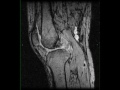

Pigmented Villonodular Synovitis, Knee

35-year-old male with chronic left knee pain. The images demonstrate a proton density isointense, STIR mildly hypointense lesion with scattered regions of signal loss. The lesion heterogeneously enhances and is intimately associated with the posterior cruciate ligament. These imaging findings are characteristic of pigmented villonodular synovitis or PVNS for short. PVNS is a benign proliferative condition affecting the synovial membranes of joints, bursa, or tendons. It results from neoplastic synovial proliferation with villous and nodular projections with scattered hemosiderin deposition. It is most common monoarticular. Occasionally, PVNS can look like aggressive neoplasms such as rhabdomyosarcoma, synovial sarcoma, or epithelial sarcoma.